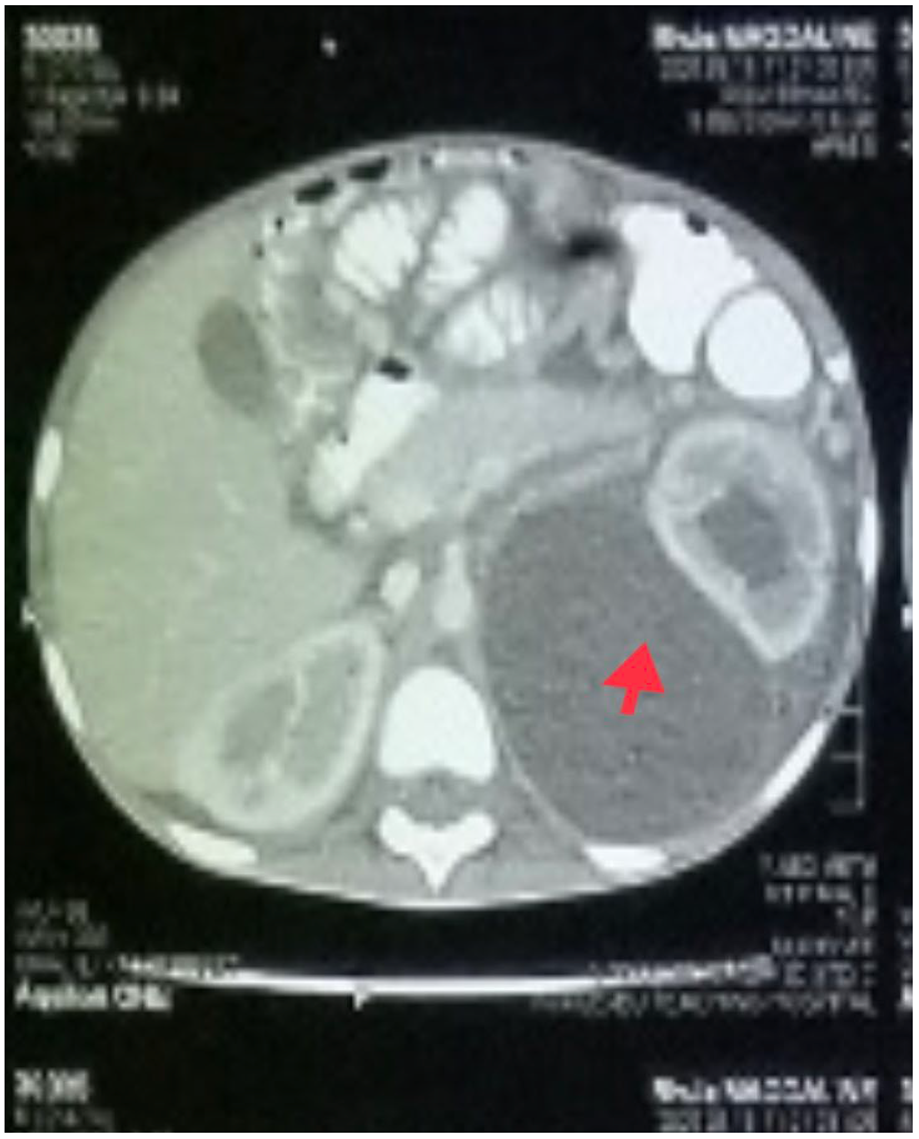

The patient was admitted to the pediatric intensive care unit (PICU) because of tachypnea, hypoxemia, and subcostal retraction. An urgent chest X-ray revealed a right pleural effusion (Figure 1).

Figure 1. Chest X-ray of the patient showing right pleural effusion.